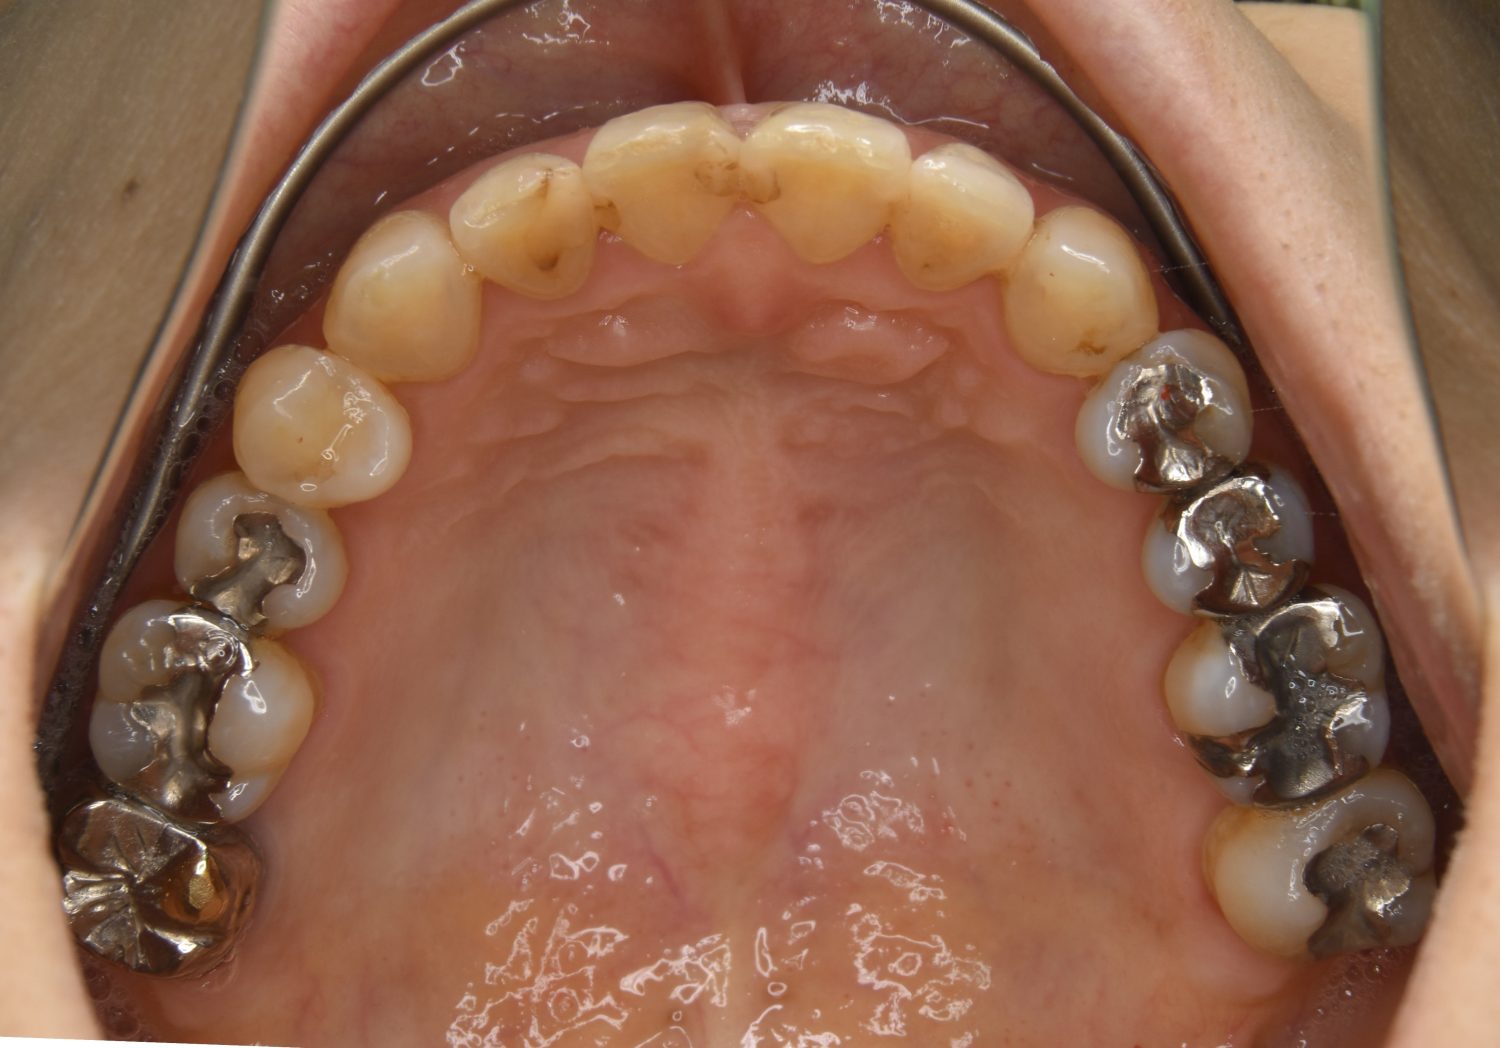

叢生の症例紹介②

Before

After

主訴

歯の凸凹を治したい。

治療内容

アライナー(インビザライン)にて非抜歯で治療を行いました。

上下前歯部に叢生(凸凹)が認められる状態でした。歯列の遠心移動を行うことで機能面および審美面が改善されました。